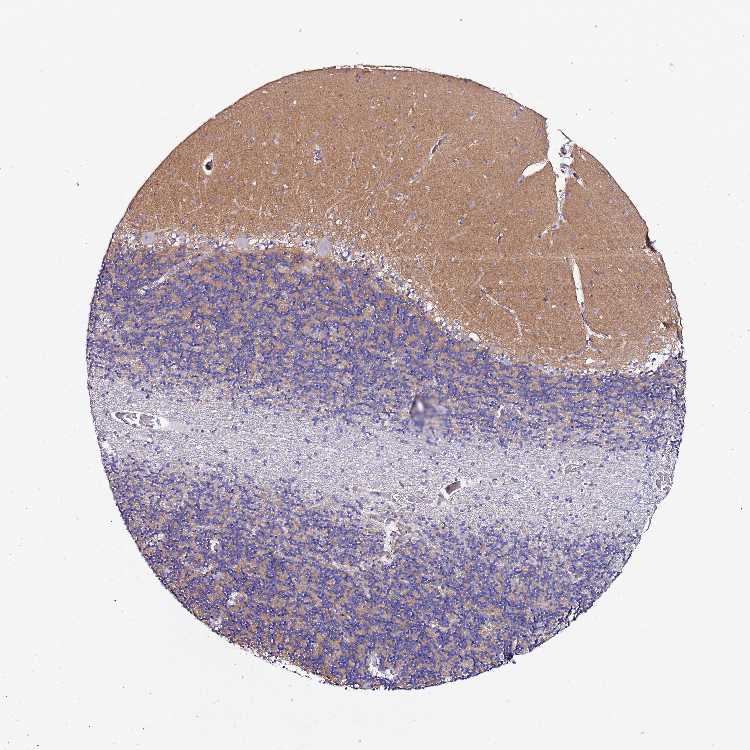

BRAIN CEREBELLUM Show tissue menu

CEREBELLUM - Expression summary

CEREBELLUM - Antibody stainingi

Antibody staining in the annotated cell types in the current human tissue is reported as not detected, low, medium, or high, based on conventional immunohistochemistry profiling in selected tissues. This score is based on the combination of the staining intensity and fraction of stained cells.

Each image is clickable and will lead to virtual microscopy that enables deeper exploration of all samples and also displays staining intensity scores, fraction scores and subcellular localization as well as patient and tissue information for each sample.

Antibody HPA045292

Purkinje cells Not detected

Cells in granular layer Not detected

Cells in molecular layer Not detected